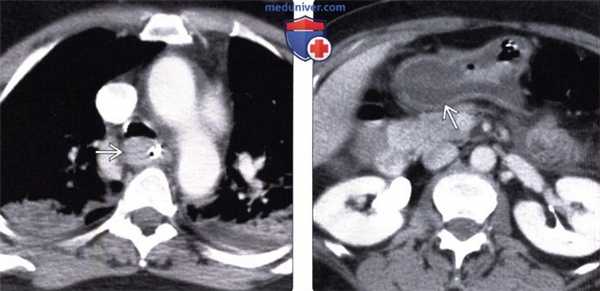

(Слева) На аксиальной КТ, выполненной пациенту через два часа после приема внутрь химического агента, определяется выраженное утолщение стенки пищевода, а также двухсторонний аспирационный пневмонит.

(Справа) На аксиальной КТ с контрастным усилением у этого же пациента определяется значительное утолщение стенки желудка и отек подслизистой основы, что является проявлением коррозивного гастрита.